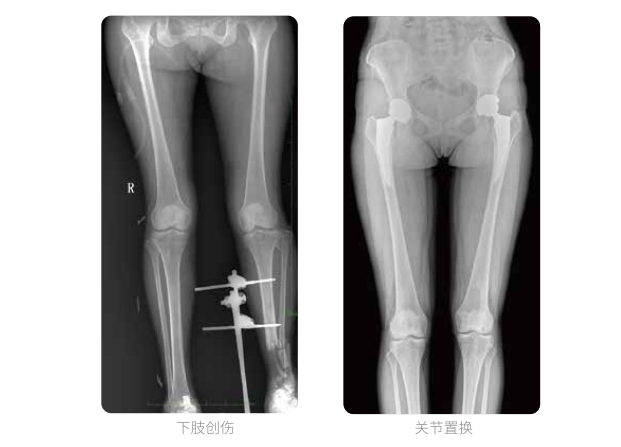

近年来,脊柱及下肢畸形的患者较多,多发于青少年的脊柱侧弯畸形,骨性关节炎、风湿性关节炎以及双下肢畸形如膝关节内外翻、X型O型腿等也是骨科常见病。并且发病率呈现逐年升高的趋势,常常累及下肢髋、膝、踝3个负重关节,影响患者生活,甚至丧失工作能力。

在脊柱及下肢畸形的临床治疗过程中,一般需要进行矫正手术治疗,在对其进行手术前后,均需要拍摄X光片以便分析病情、明确诊断和观察治疗效果。常规DR拍摄面积有限,最大规格仅有43cm,但成人男性全脊柱长度平均为70-75cm,女性为66-70cm,而双下肢更长。普爱医疗PLX8600动态DR的43cm*86cm超大有效视野,可一次性拍摄全脊柱、双下肢的影像视野。

普爱医疗动态数字化X线摄影(动态DR)拥有43cm*86cm超大有效视野,使全脊柱及双下肢能够得到完整清晰的成像,为临床在脊柱侧弯畸形和下肢骨关节病变诊断、治疗方案制定及治疗后复查提供精准的测量。

双下肢临床影像

普爱医疗动态数字化X线摄影(动态DR)可以整体显示双髋至双踝关节,直观的展示因关节软骨磨损和软组织不平衡所造成的畸形及力线异常,全面对比了解双下肢的病变情况。对于下肢矫正和人工关节置换术的术前计划,术后观察有着重要的临床意义。

普爱医疗动态数字化X线摄影(动态DR)一次成像不拼接,解决了拼接图像存在密度不均匀,拼接处图像配准和放大效应等问题,给临床带来了真正的大视野影像解决方案,高清画质,准确成像不失真,辅助医生准确诊断疾病。